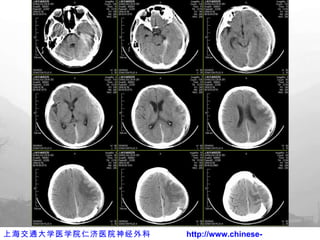

术后出院前 CT

术后 3D CT

颅骨修补

颅骨修补术后

例 2  男性 32 岁,修补术后 CT